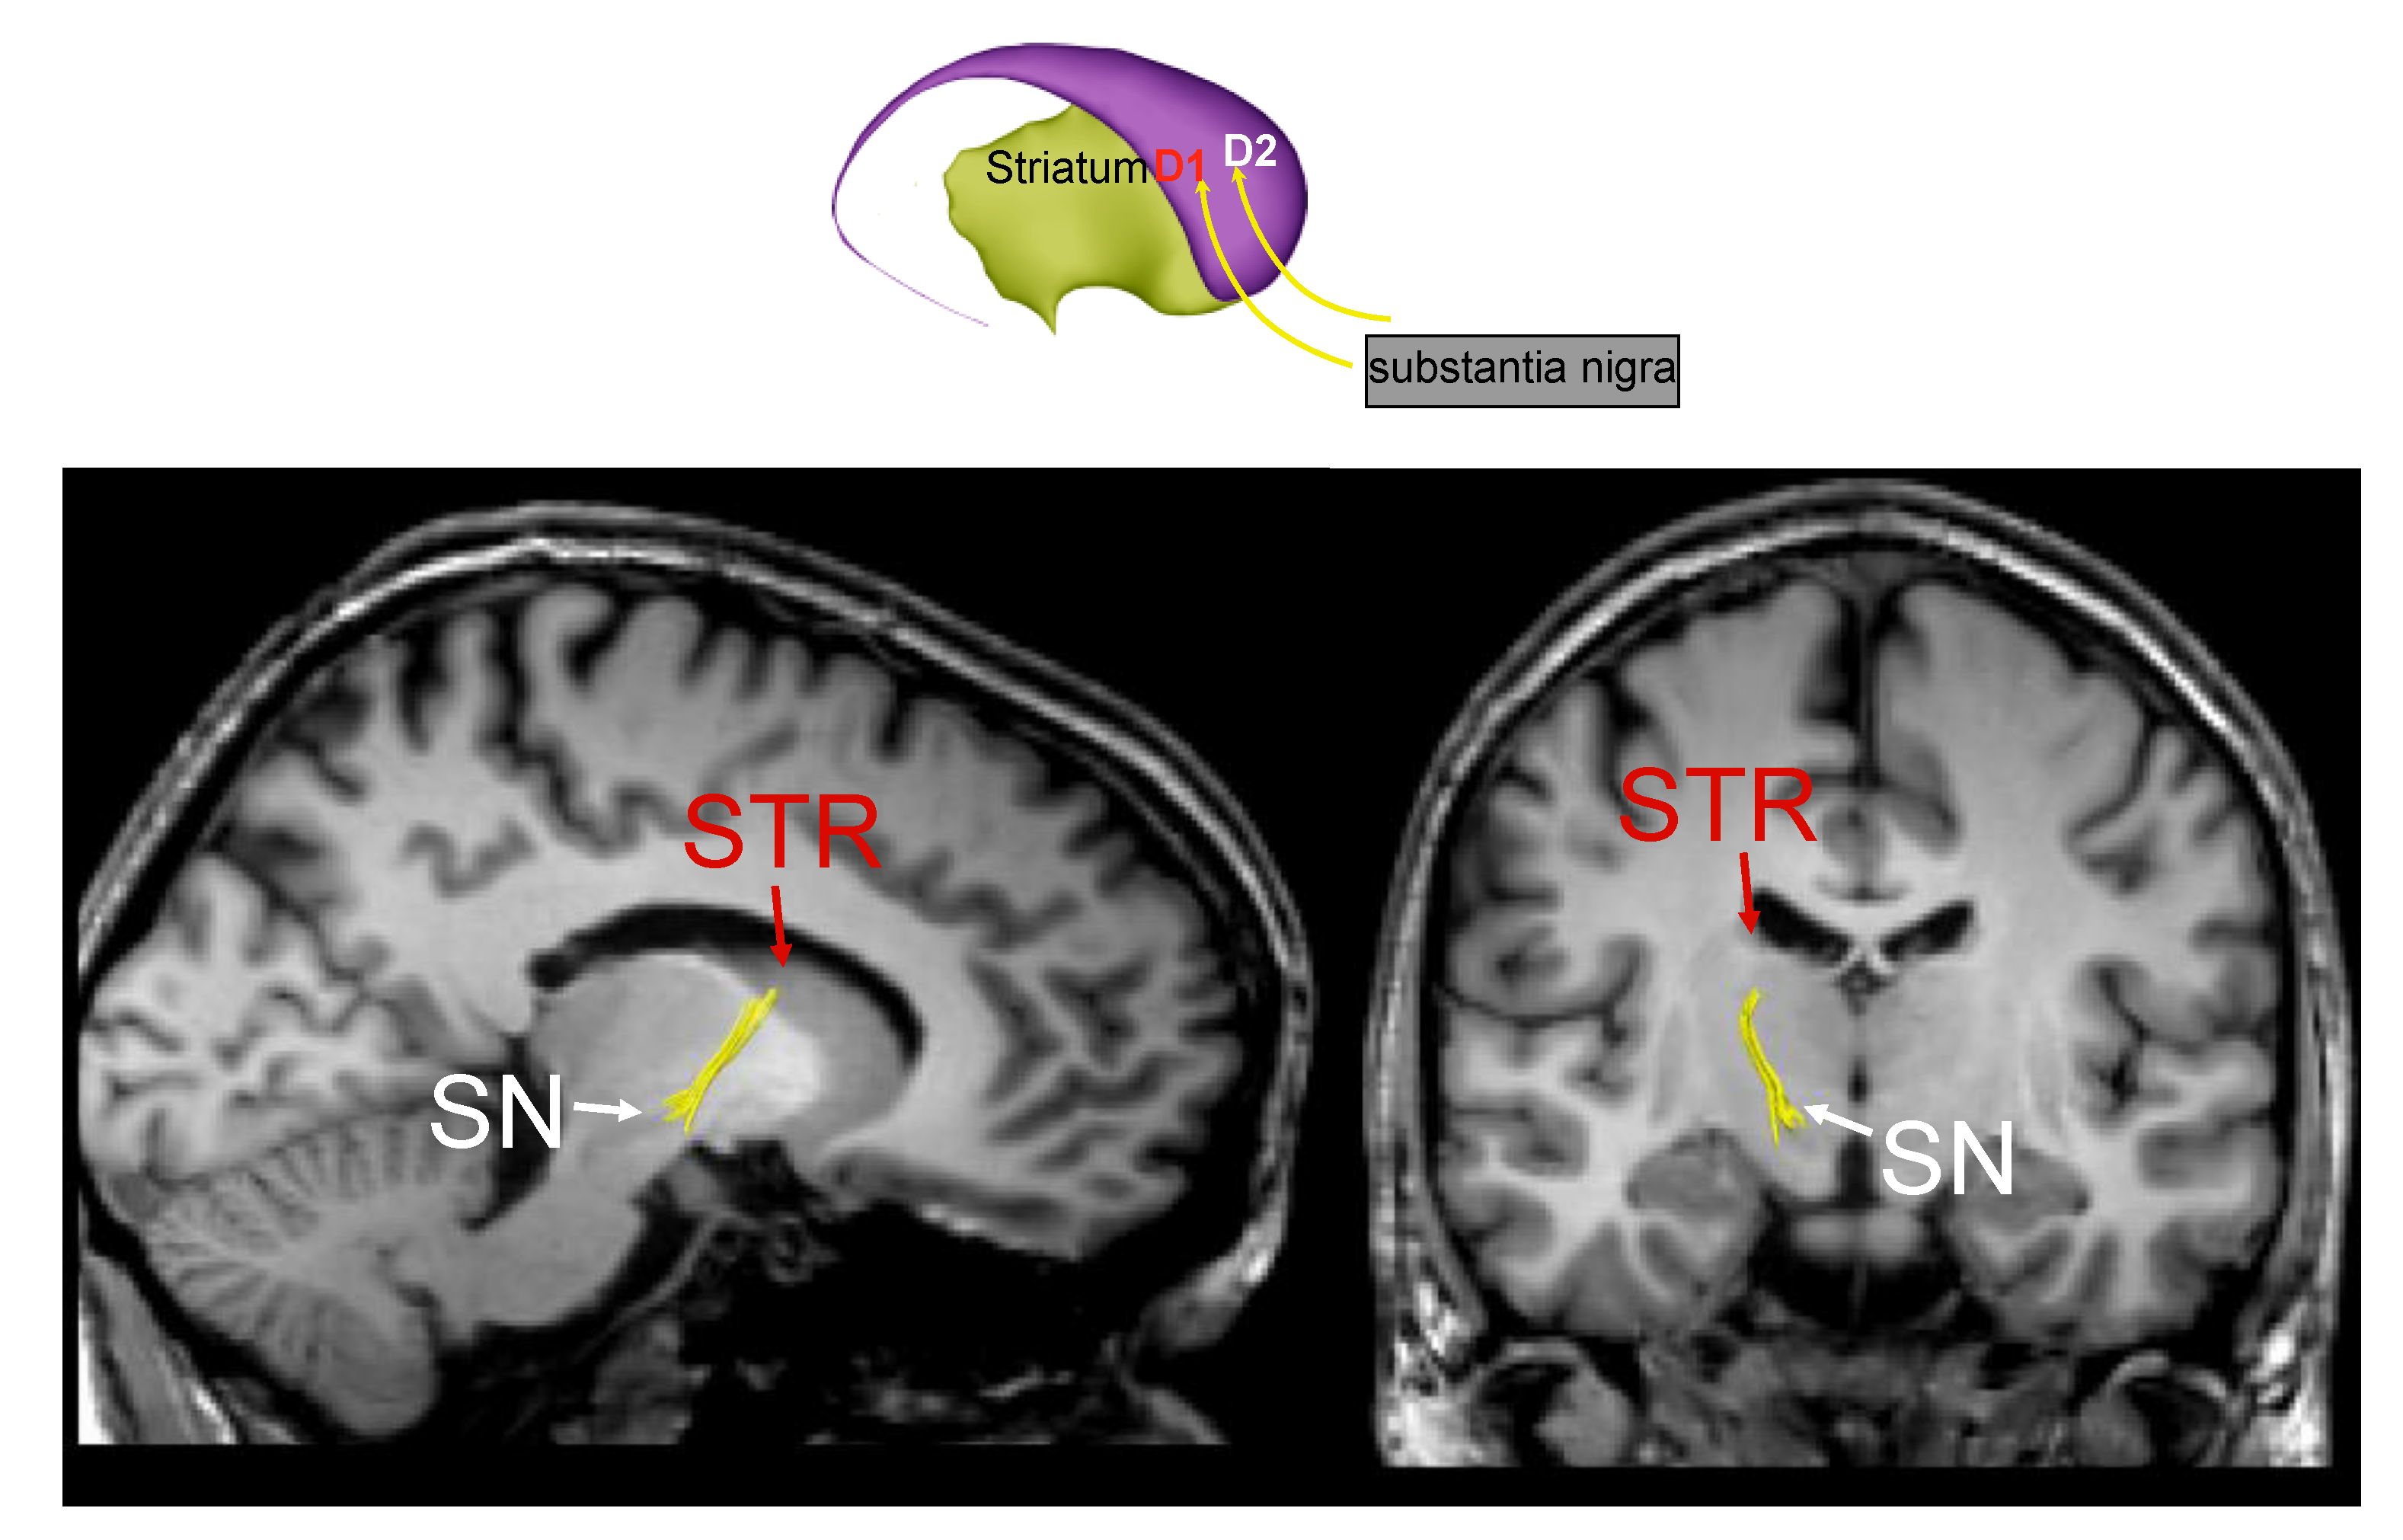

2.1. Structural Magnetic Resonance Imaging (sMRI)

3. Parkinson’s Disease Subtypes Identified by Tractography